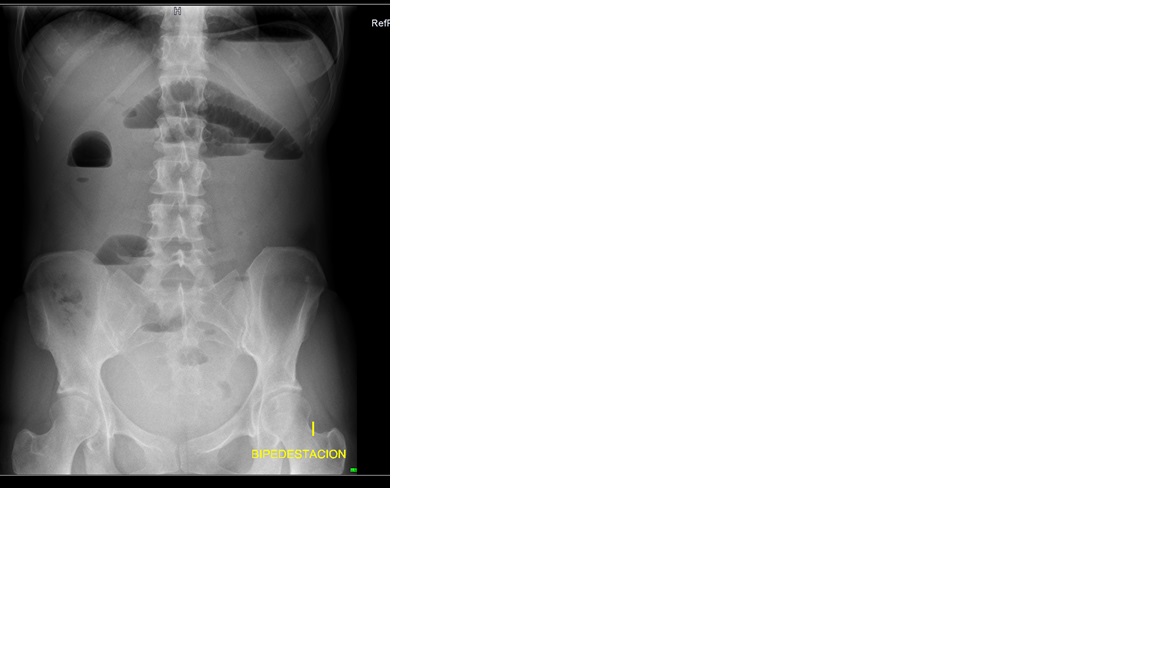

Rx abdomen: niveles hidroaéreos, dilatación de asas de delgado, de hasta 3,5 cm; no se observa gas en colon.